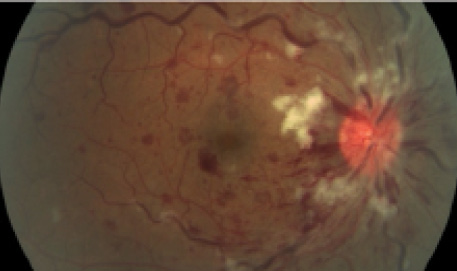

On examination, moderate optic disc swelling was noted OD, and more significant optic disc edema accompanied by diffuse superficial hemorrhages was observed in all four quadrants OS (Figure 2). Fluorescein angiography was significant for marked venous staining and leakage, in addition to leakage and late staining from the optic disc. Optical coherence tomography (OCT) was not clinically available at the time of initial diagnosis. Systemic and hematologic examinations were ordered and returned positive for Glanzmann thrombasthenia (GT) and hepatitis C virus infection. GT is a rare, autosomal recessive coagulopathy characterized by either qualitative or quantitative abnormalities of the membrane glycoprotein αIIbβ3 complex, which result in bleeding tendencies that range from purpura to life-threatening hemorrhage.

Figure 1. Case No. 1: Moderate optic nerve disc swelling present OD (A). Red-free image showing typical presentation of papillophlebitis OS, including edema of the optic disc, retinal venous engorgement, and perivenous retinal hemorrhages (B).